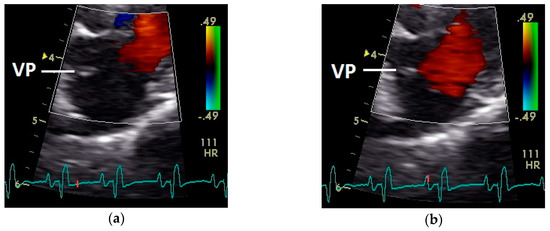

Figure 7.

Position of the valva pulmonis (VP) in the diastole: (a) passive and (b) active ventricular filling (red signal); HR: heart rate; color scale of the color Doppler image is calibrated in m s−1.